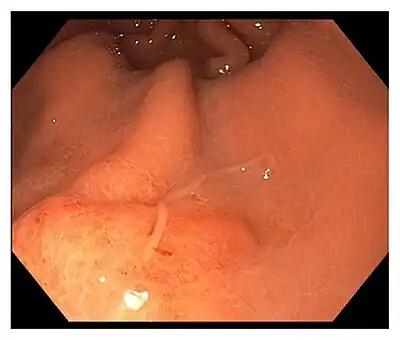

A typical endoscopy of the acute gastric form shows a worm embedded within the submucosa, with a visible lesion at the site of entry, and a thicker oedematous stomach lining.[3] In patients with chronic gastric infection, there is often an ulcer or inflamed mass visible on the stomach lining.[3]

The worm is often removed during the gastrointestinal endoscopy, which alleviates the symptoms within hours.[3][7] However, surgical removal of the affected tissue must be conducted when the worms are already buried deep in the viscera.[3][7]